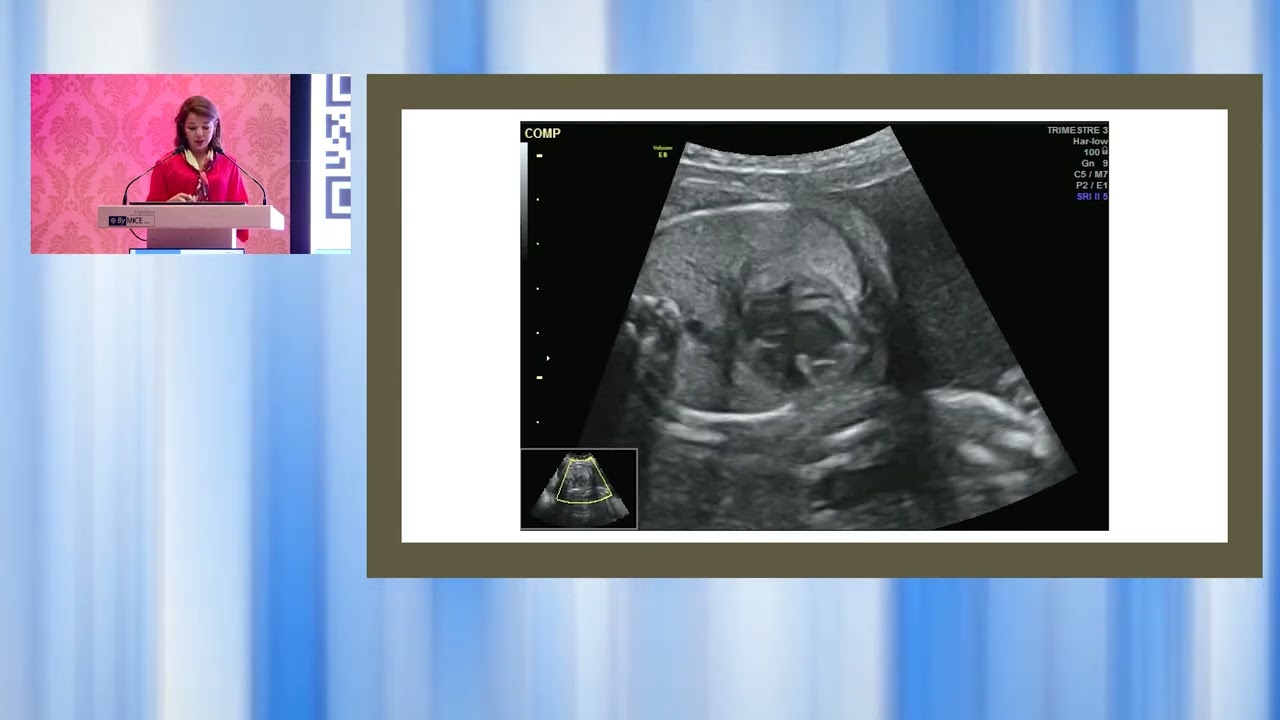

Les Journées d'échographie Septembre 2024 : Coupe des 4 cavités normale : Dr Gargouri Rania